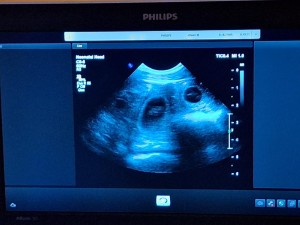

BŘEZOST POTVRZENA

Dnes jsme dostali, trošku v předstihu, nádherný vánoční dárek.

Dopoledne jsme byli s Emičkou

na sonu. Nejprve jí dělala paní doktorka sono ve stoje, ale říkala, že jsou ve stoje ta miminečka vidět hůř. Takže jsme Emičku položili, což byl jako vždy nadlidský úkon, ona je neskutečně hysterická, ale nakonec se nám to podařilo a doktorka se mohla na tu nadílku podívat. A konečný verdikt zněl 5 až 6 štěňátek. Takže přibližně v polovině ledna 2026 bude u nás veselo![]()